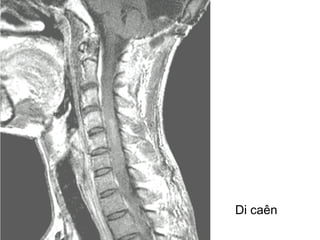

Di caên

Di caên coät

soáng